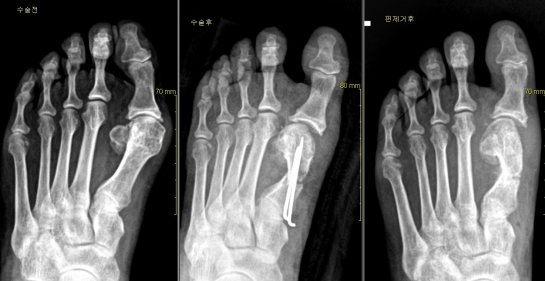

A. 무지 외반증의 가장 좋은 치료는 수술입니다. 물론 증상이 경미하고, 변형이 심하지 않은 경우 볼이 넓고 편안한 신발이 통증 완화에 도움을 주며 시중에 많이 나와있는 보조기, 기능성 신발이나 기능성 깔창은 일시적으로 통증을 줄여줄 수 있으나 변형이 교정되거나 근본적인 치료는 기대할 수 없습니다. 가장 효과적인 치료법은 수술입니다. 수술은 변형된 발을 절골술과 박리술을 통해 정확한 교정이 가능하며, 이로 인해 발의 기능과 모양의 향상을 이룰 수 있습니다

A. 수술은 약 1시간 30분 정도 소요되며, 타 수술에 비해 그 후유증이나 재발율이 매우 적은 편이다. 최근 절골술을 이용한 수술 기법이 발달하여 결과가 매우 우수합니다.